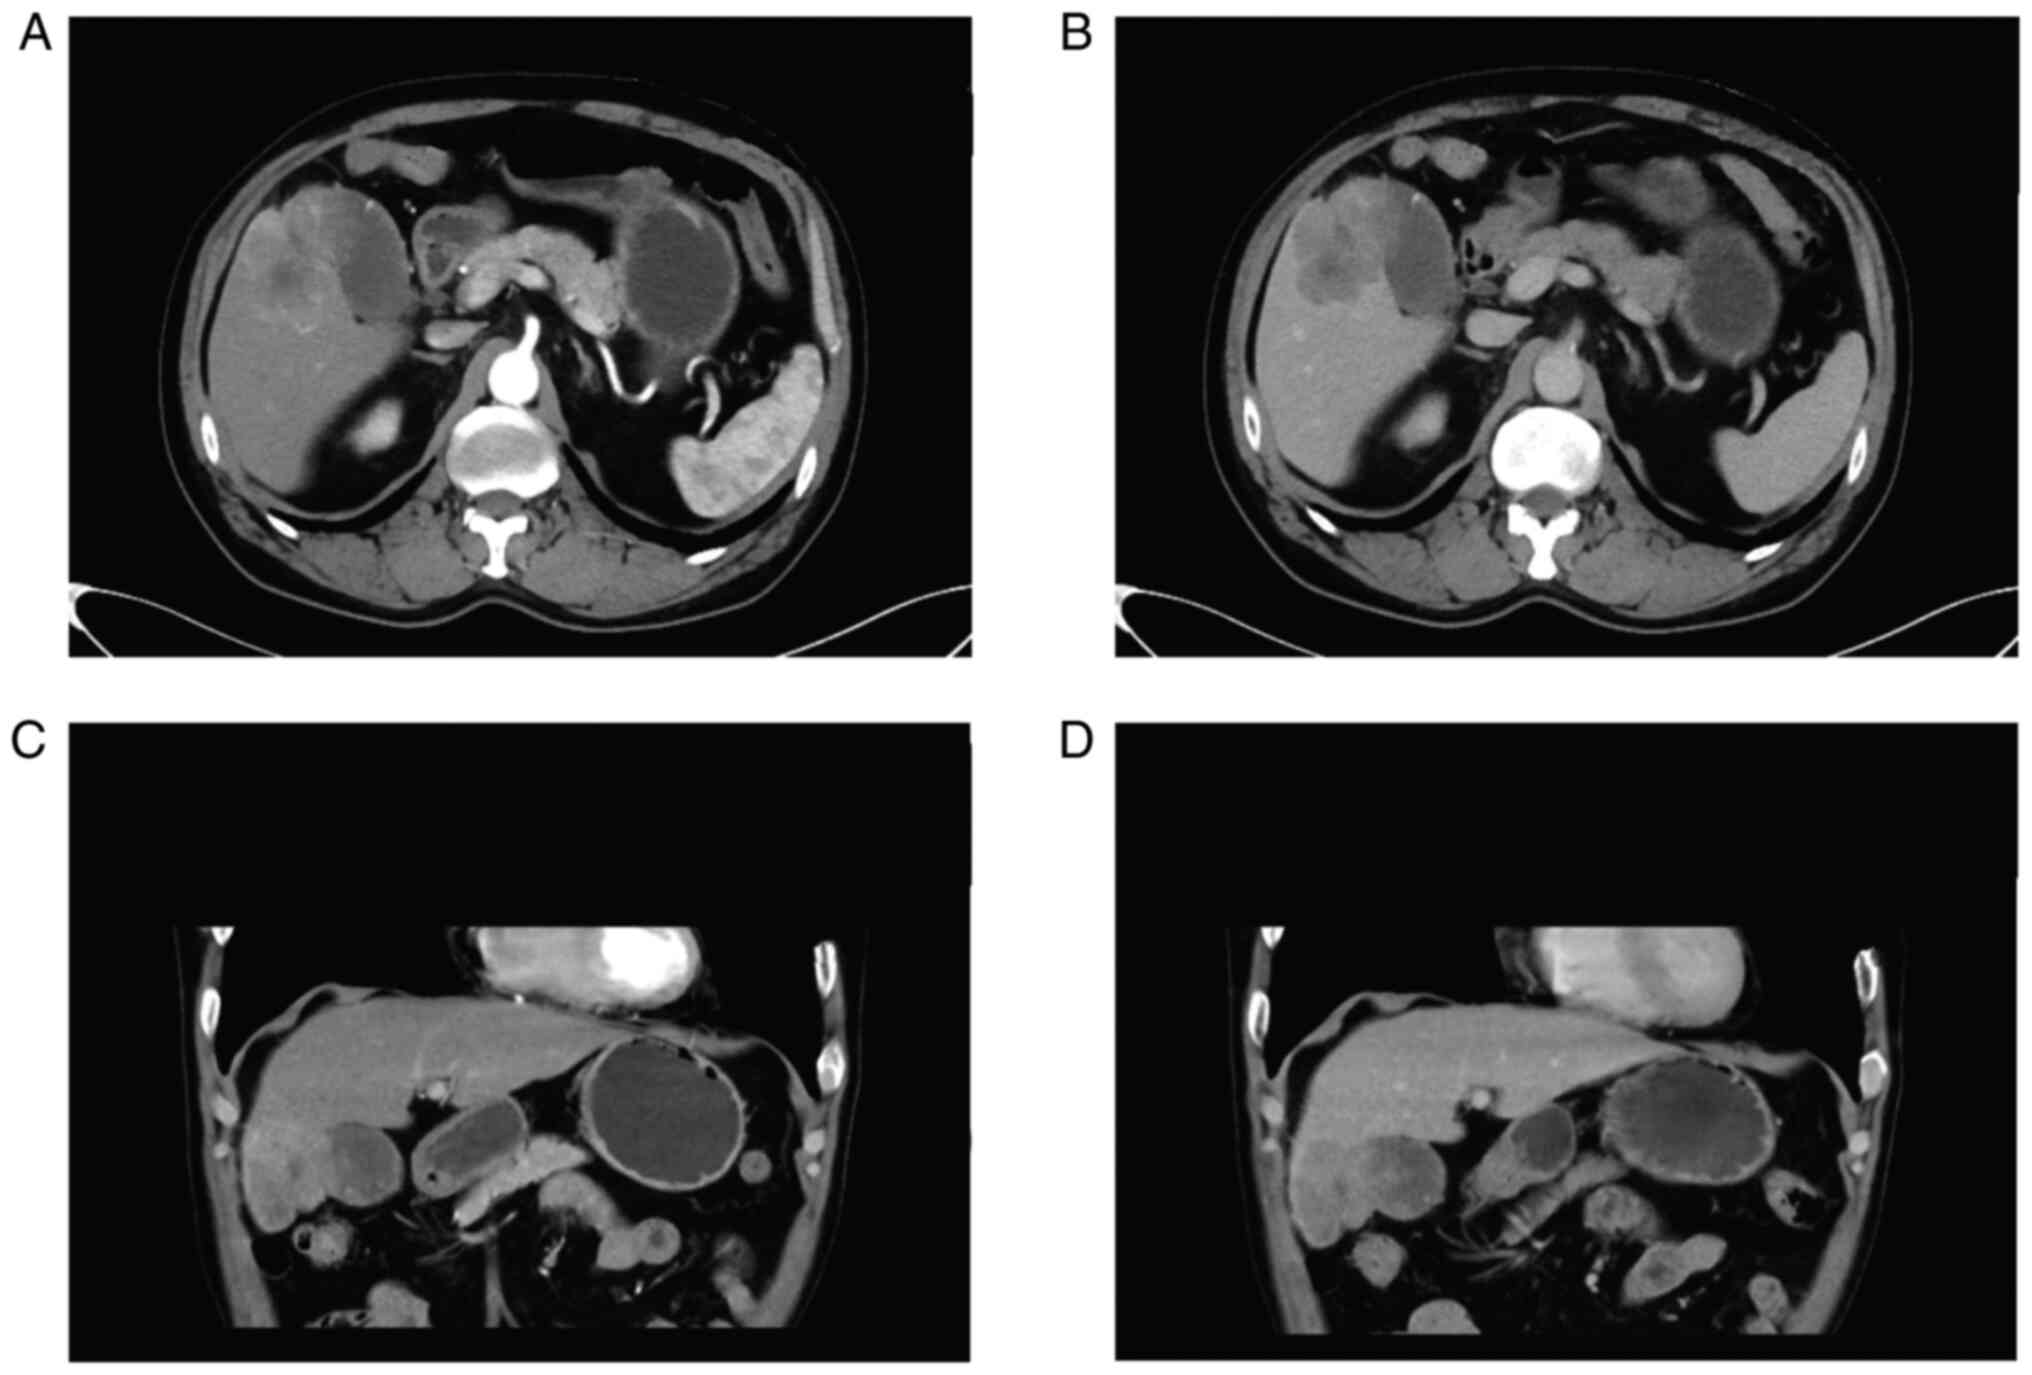

The case was a 66-year-old male patient presented to our hospital with paroxysmal upper abdomen pain for more than half a year. The day before the visit, the patient presented a worsening of upper abdomen pain accompanied by nausea and vomiting. Also, the patient experienced loss of appetite and weight loss over 5 kg in the past 6 months. Partial gastrectomy was performed 4 years ago owing to esophageal carcinoma. Abdominal ultrasound suggested thickening of the gallbladder wall and a liver cyst. CT scanning of upper abdomen showed marked signal abnormality in the gallbladder (Fig. 4). Levels of tumor markers were showed in Table I. These results indicated suspected gallbladder cancer.

Figure 4.

CT images of case 2. (A) Cross-sectional contrast-enhanced arterial phase CT of the abdomen. (B) Cross-sectional contrast-enhanced venous phase CT of the abdomen. (C) Contrast enhanced arterial phase CT scan of the abdomen, coronal view. (D) Contrast enhanced arterial phase CT scan of the abdomen, coronal view. CT, computed tomography.